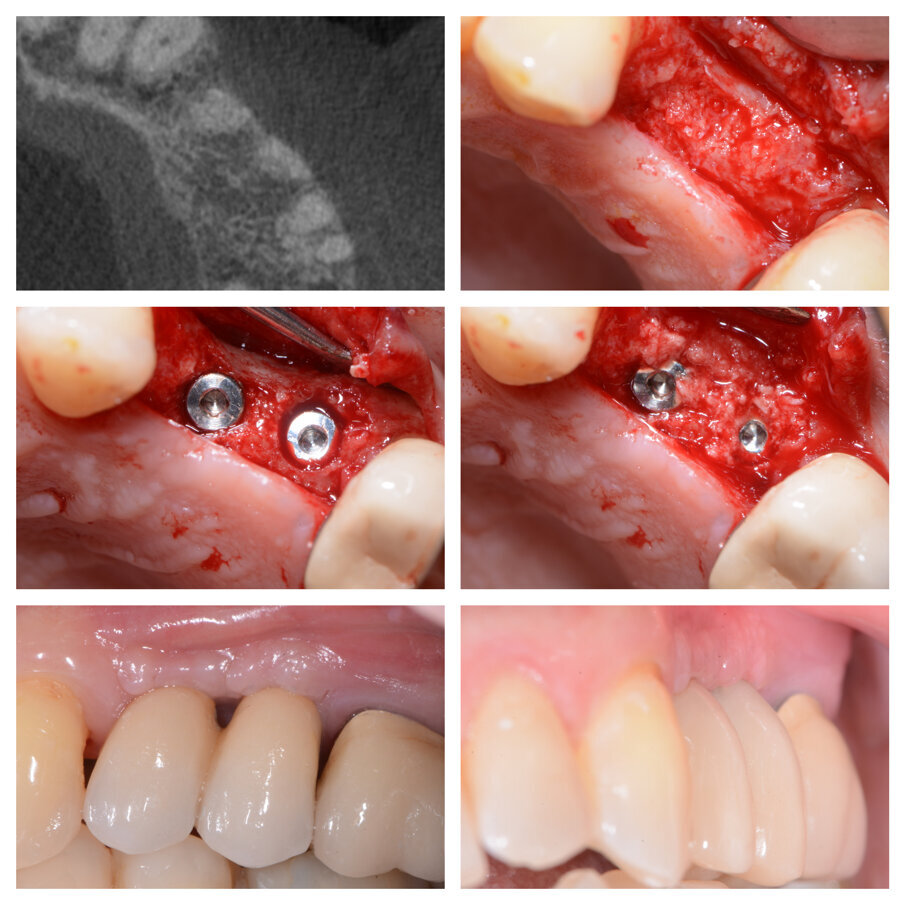

Fig. 6a_Perdita di elemento di ponte 24 e deficit in zona 25, fasi chirurgiche e guarigione.

Fig. 6b_Rientro chirurgico per il posizionamento implantare e protesi definitiva.

Tutti gli interventi eseguiti con questa tecnica, nove in tutto, hanno portato alla risoluzione del deficit orizzontale presente al momento dell’estrazione, e hanno permesso in tutte le zone trattate un buon inserimento implantare senza la necessità di ulteriori tecniche di GBR (Figg. 1d, 3a, 3d, 6b). Gli interventi sono stati eseguiti sia in mandibola che nel mascellare superiore, trattando edentulie singole e multiple. Non eseguendo lembi di scarico e scollando il meno possibile, i pazienti nei giorni successivi non presentano particolare gonfiore; anche il dolore è molto limitato e gestibile con poche dosi di antidolorifico per via orale, oltre la terapia antibiotica con Amoxicillina 875 mg. e Acido Clavulanico 125 mg. ogni 12 ore per sei giorni. Il primo caso risale al gennaio 2011 ed abbiamo quindi un controllo a più di 4 anni dal posizionamento implantare (Fig. 7). La stabilità dei tessuti duri e molli è risultata buona, non avendo perso alcun impianto e soprattutto non avendo casi di perimucosite-perimplantite.